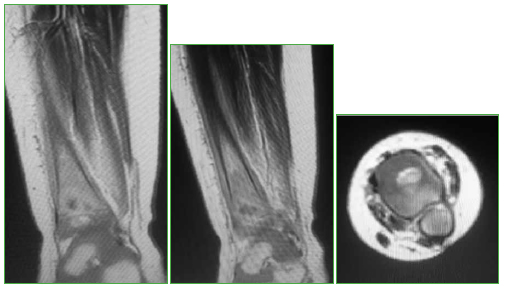

Lipoblastoma: una causa inusual de tumoración del pie en niños

65-73

Acceso mediante suscripción PDF Acceso mediante suscripción PDF_EN (English) Acceso mediante suscripción Figura 1 Acceso mediante suscripción Figura 2 Acceso mediante suscripción Figura 3 Acceso mediante suscripción Figura 4 Acceso mediante suscripción Figura 5 Acceso mediante suscripción Tabla 1 Acceso mediante suscripción HTML